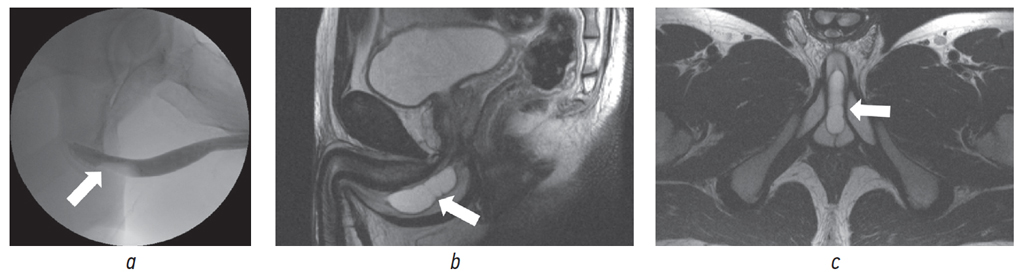

Учитывая сохраняющиеся жалобы, через 2 мес. после выписки из урологического стационара при купированном воспалительном процессе в предстательной железе пациенту было проведено дообследование с целью дифференциальной диагностики согласно представленному выше алгоритму с выполнением восходящей уретрографии, МРТ малого таза и наружных половых органов, уретроскопии (рис. 6).

Рис. 6. Пациент Ш., 19 лет: а — восходящая уретрограмма, определяется дефект наполнения, соответствующий расположению бульбоуретральной кисты (указан стрелкой); b, c — магнитно-резонансная томограмма малого таза, в двух проекциях определяется кистозное образование — сирингоцеле с тонкими перегородками (указано стрелками)

Fig. 6. Patient Sh., 19 years old: a – ascending urethrogram of the filling defect corresponding to the location of the bulbourethral cyst is determined (indicated by the arrow); b, c – magnetic resonance imaging of the small pelvis, in two projections a cystic formation is determined – a syringocele with thin septa (indicated by arrows)

При выполнении восходящей уретрографии уретра была проходима на всем протяжении, в бульбозном отделе по вентральной поверхности определялся дефект наполнения с четкими ровными контурами размерами до 0,4 × 4,0 см без затеков контрастного вещества с последующим попаданием препарата в мочевой пузырь (рис. 6, a).

По данным МРТ на 3,5 см дистальнее шейки мочевого пузыря парауретрально по срединной линии визуализировалось кистозное образование, не сообщающееся с мочеиспускательным каналом, размерами 4,2 × 1,3 × 1,5 см. Внутренняя структура кисты разделена тремя тонкими перегородками с однородным жидкостным содержимым.